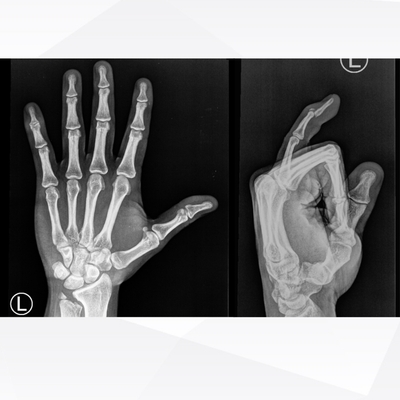

Click on an image below to view more info.